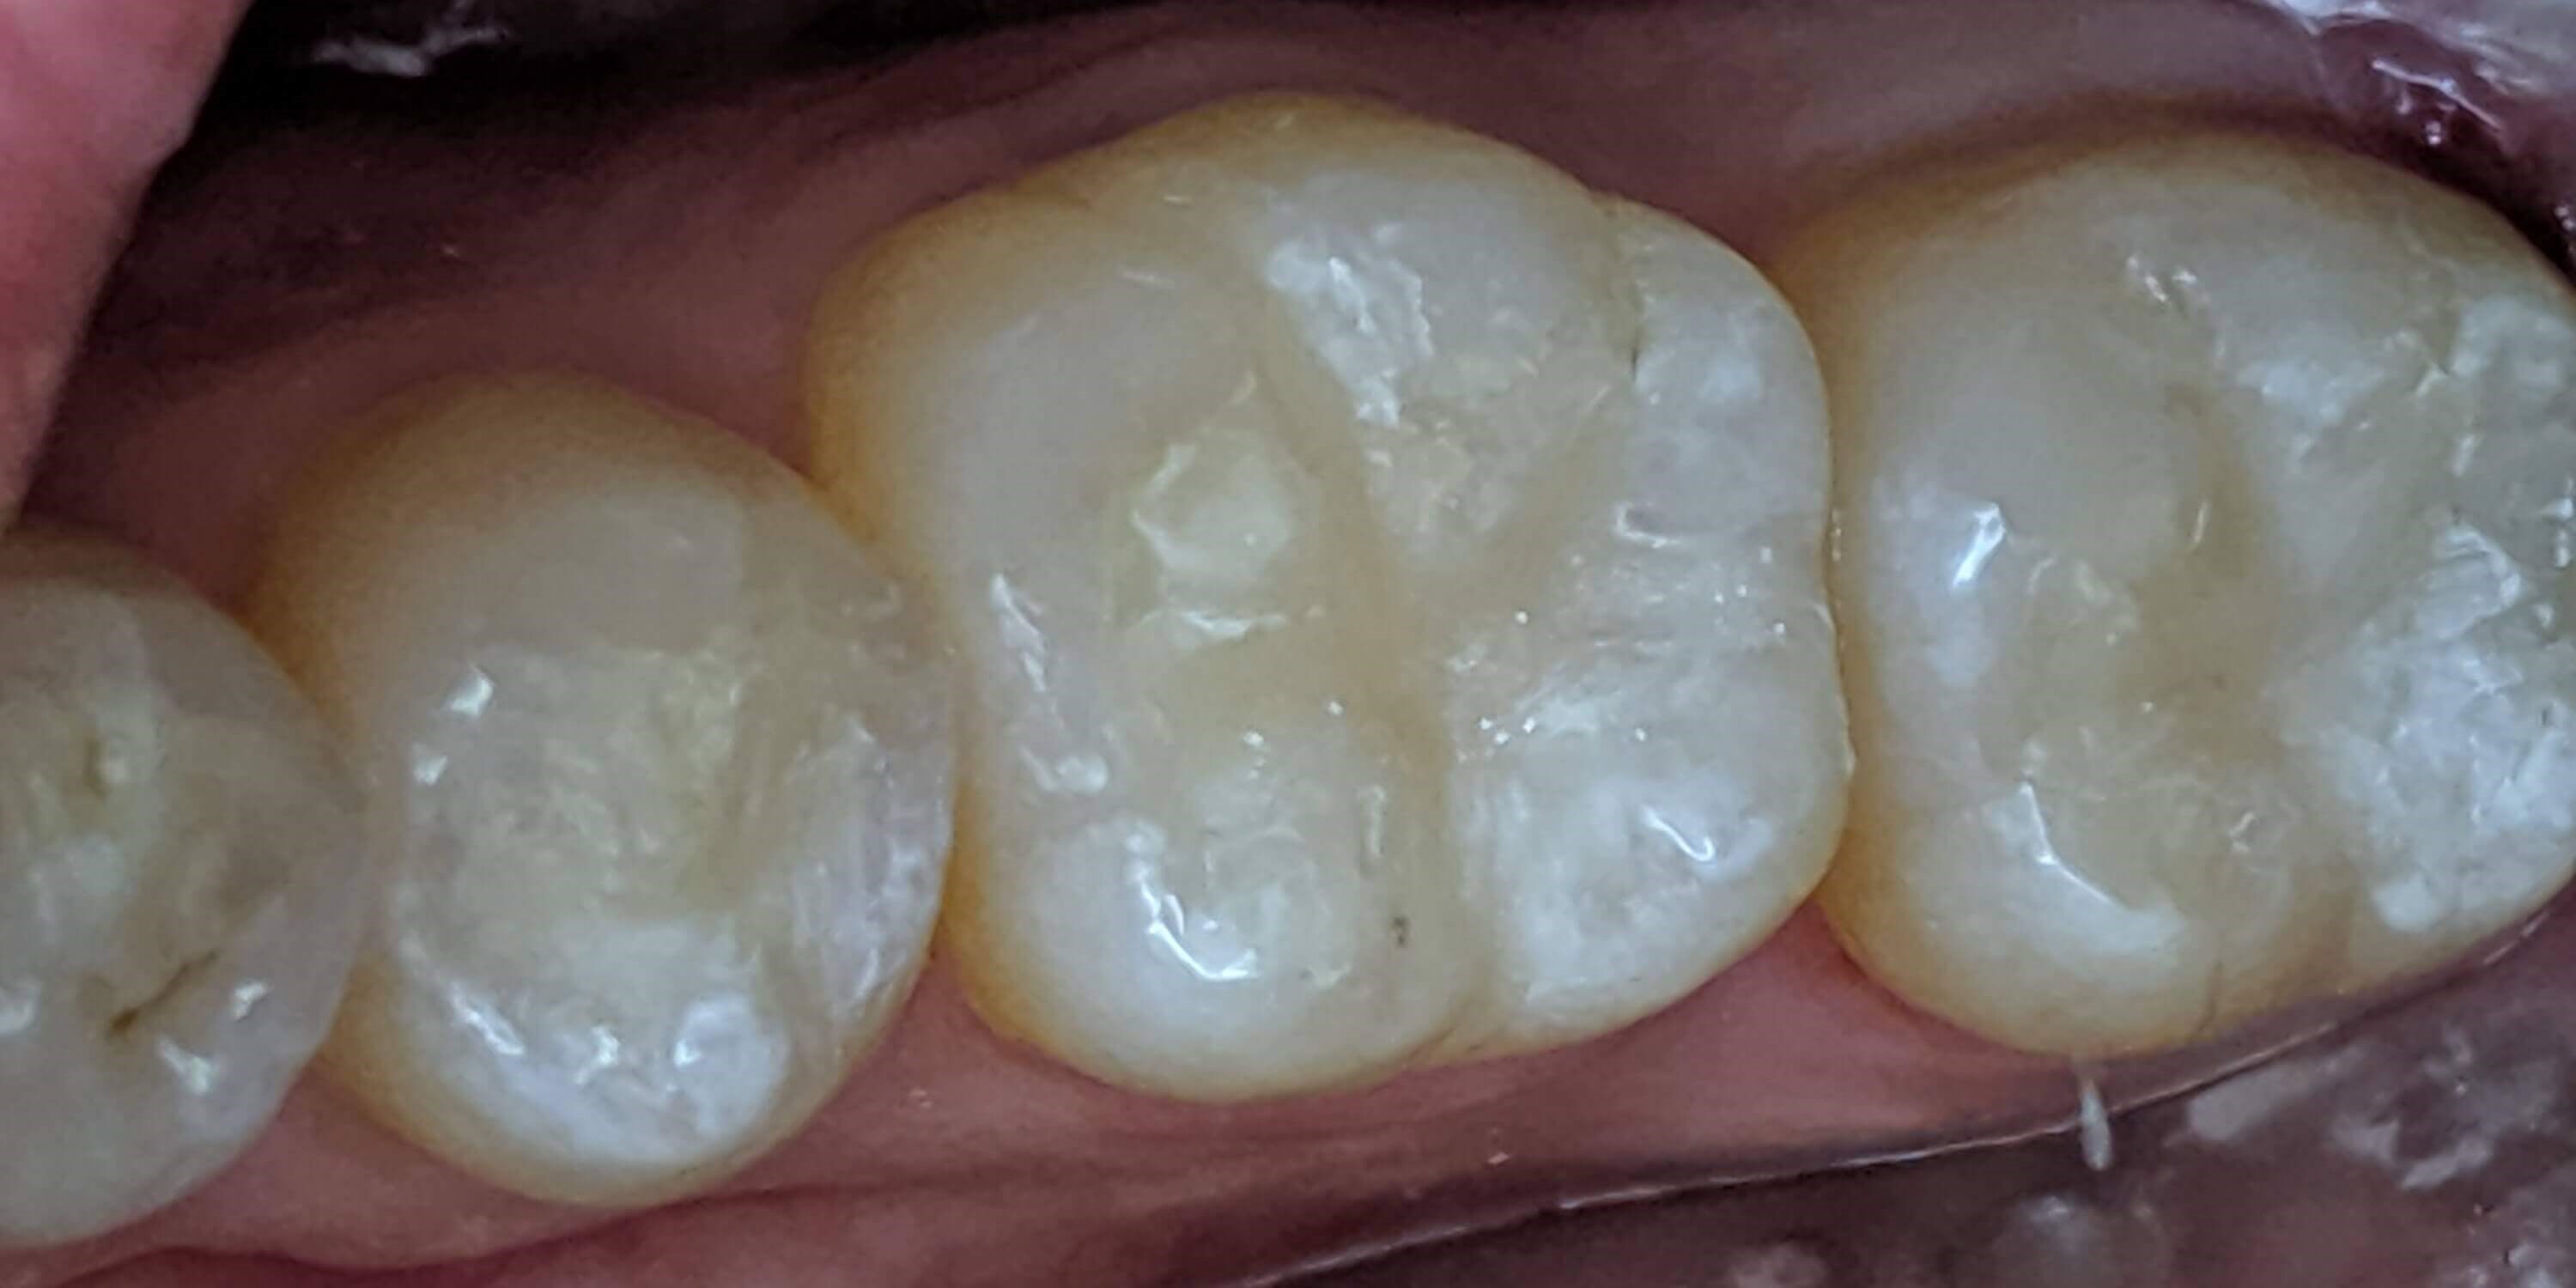

Tooth-colored fillings often fill in the decay in the enamel after it has been cleaned. Composite resin is a versatile material that can be used to treat other problems with your teeth, including cracks or enamel that has been worn down by teeth grinding (bruxism). Since the composite resin is colored to match your natural teeth, tooth-colored fillings can be used on both the front and back teeth for a seamless appearance. If you have metal fillings, talk to Dr. Kim or Dr. Chang about having them removed and replaced with tooth-colored fillings.

Getting a filling at Luminous Dental Studio is typically an easy process. The area surrounding the cavity will be numbed with a local anesthetic to minimize your discomfort. Other forms of sedation can be discussed if you have any fears or dental anxieties to help keep you at ease during the procedure. Once you are prepared, the decayed enamel is removed with a unique dental drill that Dr. Kim or Dr. Chang will select based on where the cavity is located in the tooth and the level of decay. After the enamel is removed and the tooth is cleaned, the cavity will be filled with the composite material and set with a special light. Dr. Kim or Dr. Chang will polish the filling so it feels comfortable and matches your natural teeth.

Yes, they do. The main benefit of tooth-colored fillings is the fact that they don't change the natural color of your tooth — so no one but you will know you have a filling.